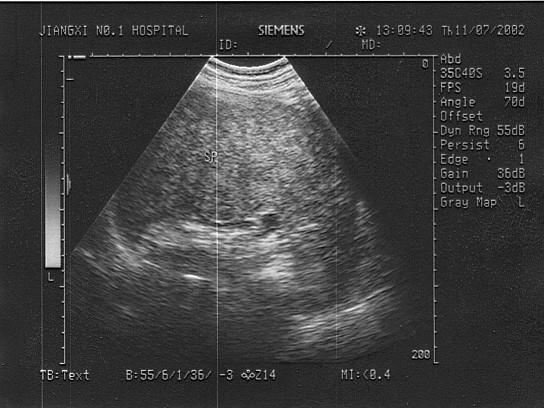

男,35岁、有淋巴瘤病史。结合超声声像图,诊断为?(?)A.脾转移性肿瘤B.脾结核C.脾包虫病D.脾梗死E.脾脓肿

问题 男,35岁、有淋巴瘤病史。结合超声声像图,诊断为?(?)

选项 A.脾转移性肿瘤 B.脾结核 C.脾包虫病 D.脾梗死 E.脾脓肿

答案 A